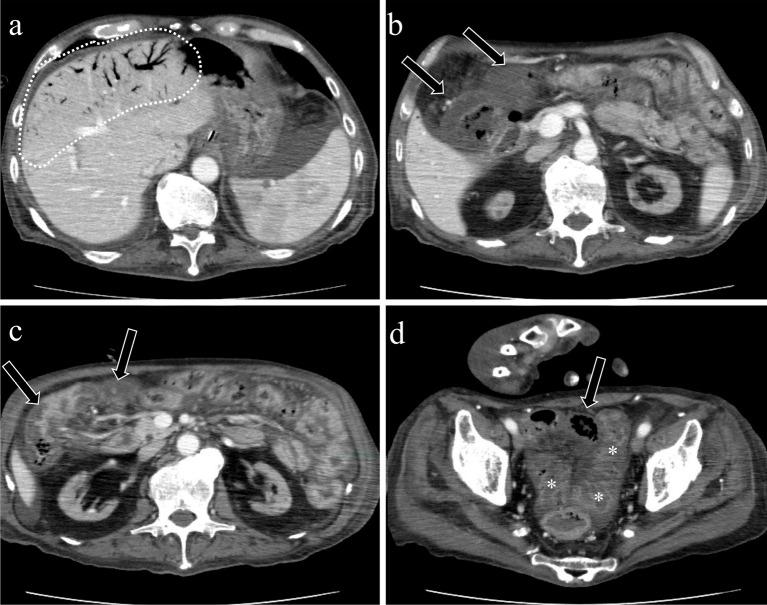

Acute mesenteric ischemia is a life-threatening condition. A comprehensive approach involving a multidisciplinary team to review patient background, clinical history, physical examination, laboratory data, and imaging examination for respective diagnosis of superior mesenteric arterial occlusion, nonocclusive mesenteric ischemia, and superior mesenteric venous occlusion is essential. The most important imaging modality is computed tomography, which is used for diagnosis and for directing therapeutic strategy (e.g., endovascular revascularization, surgical bowel resection, or conservative management). Computed tomography image findings can support triaging of irreversible transmural bowel necrosis compared with reversible ischemic change with reperfusion. In this review article, the computed tomography imaging findings specifically associated with the pathophysiology of superior mesenteric arterial occlusion, nonocclusive mesenteric ischemia, and superior mesenteric venous occlusion are reviewed.

急性肠系膜缺血是一种危及生命的疾病。采用多学科团队的综合方法来审查患者背景、临床病史、体格检查、实验室数据以及影像学检查,以分别诊断肠系膜上动脉闭塞、非闭塞性肠系膜缺血和肠系膜上静脉闭塞至关重要。最重要的影像学检查方法是计算机断层扫描,它用于诊断并指导治疗策略(如血管内血运重建、手术肠切除或保守治疗)。计算机断层扫描图像结果有助于区分不可逆的透壁性肠坏死与可通过再灌注逆转的缺血性改变。在这篇综述文章中,将对与肠系膜上动脉闭塞、非闭塞性肠系膜缺血和肠系膜上静脉闭塞的病理生理学具体相关的计算机断层扫描影像学结果进行综述。